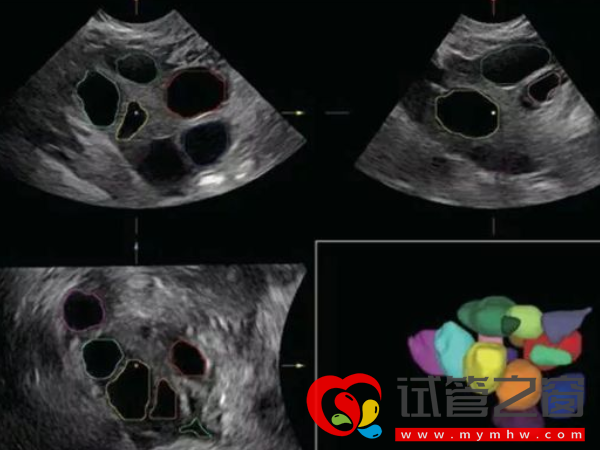

正常来讲,空卵泡通过B超是无法准确的查出。B超监测卵泡的时候看到的是含有卵泡液的卵泡腔的大小,里面有没有卵子是看不到的,因为卵子的体积很小,在超声下根本看不到。只有在进去试管助孕是,取出卵子通过放大的显微镜才能知晓是不是空卵泡。通常所说到的三种检查空泡的方式主要是:

- 1. B超:现在还没有能够100%确诊为空卵泡的检查方法,但通过B超动态监测能够大致了解是否为空卵泡,但并不能确认是空卵泡。

- 2. 阴超:阴超是可以检测卵泡的,相对B超来说,阴超检查的结果更准确,主要是从阴道进入体内,然后观察体内卵子的发育情况,但想要检查到空卵泡的话,也是不准的;

1、借助B超动态监测就可以大致了解是否为空卵泡了,如果卵泡长到18-25cm,算是发育成熟,达到这个数值一般会排出。若监测期间卵泡并没有按照这个趋势发育,如明显偏小,形状很扁,这说明卵泡可能是空卵子;